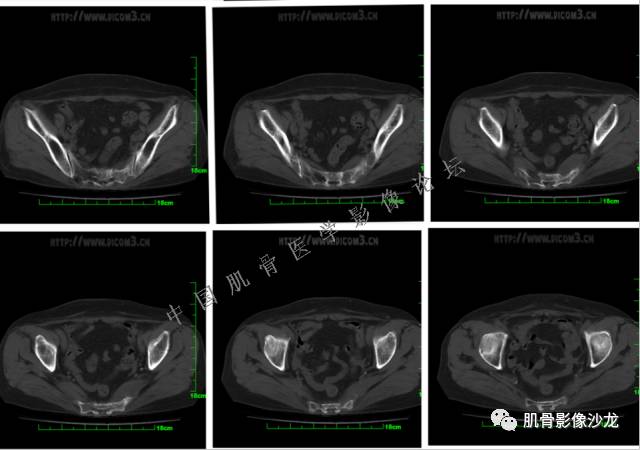

患者2月前无明显诱因下感右腿疼痛、麻木,疼痛呈持续性,发作时无法行走,休息后可缓解。当时无明显肿块,患者遂至当地医院就诊,查X片见右髂骨骨质破坏。6周前患者自觉右髋部渐大肿块,初肿块较小,后肿块逐渐增大,现肿块约12*10cm大小,有压痛。患者遂至我院就诊,查MRI:右髂骨异常信号,伴软组织肿块。ECT、肺CT未见转移。现患者为求进一步治疗,门诊拟“右髂骨肿块 ”收治入院。 患者发病来,神清,精神可,胃纳夜眠可,二便无殊,体重无明显变化。

信号 飞鹰行动:的确应该考虑软骨类肿瘤

飞鹰行动 : 第一列可以看见T2小结节样高信号,周围有纤维组织环绕

高回青 : 另外还可以见到扇贝状分叶

1、软骨肉瘤可以有膨胀性骨质破坏(病例3,4),可以有溶骨性骨质破坏(病例2),局部皮质因为破坏变薄,中断 ;

2、软骨基质T2WI高信号,软骨小叶分叶状,也就会出现高老师提到的骨内膜扇贝形压迹。一般认为骨内膜扇贝形压迹超过骨皮质厚度的2/3是软骨肉瘤在长管状骨的特征性表现。如上图。3、软组织肿块或肿胀;